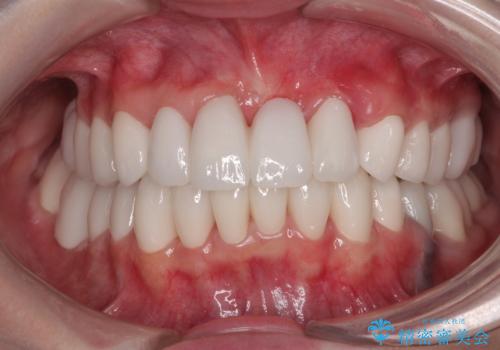

捻れて前に出ている前歯 ワイヤー装置での非抜歯矯正